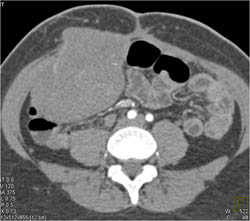

Ulcerated GIST Tumor